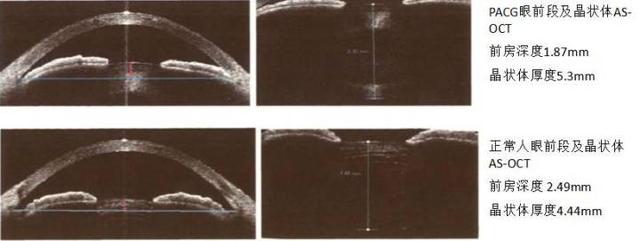

我们在进行眼部生物测量检查的时候,可以观察到患者的眼轴是短的,前房是浅的,它不一定有非常明显的白内障,但是晶状体是增厚的。这类病人除了眼部存在干眼、视疲劳,精神症状不佳甚至有睡眠障碍之外,出现青光眼的风险会明显增高。由于晶状体的增厚,会导致房水堵塞,循环受阻,造成容易发生闭角性青光眼。